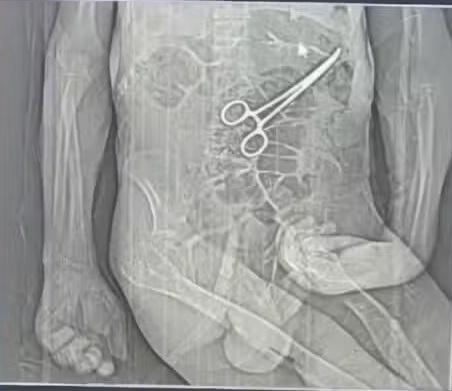

Segundo o boletim de ocorrência, registrado no dia 30 de dezembro de 2025, o filho da vítima, de 31 anos, informou que só tomou conhecimento da existência do objeto cirúrgico após a divulgação de imagens de exames por veículos de comunicação da região.

De acordo com o advogado Iuri Evangelista Furtado, que representa a família, os parentes só tiveram conhecimento da possível permanência da pinça cirúrgica após o vazamento de uma imagem de exame para uma rádio local, mostrando o objeto no interior do corpo do paciente.

Ainda segundo o defensor, a Prefeitura de João Pinheiro chegou a emitir uma nota informando a identificação de um “corpo estranho”, sem especificar que se tratava de uma pinça cirúrgica. A confirmação, segundo ele, só ocorreu após a divulgação pela imprensa local.